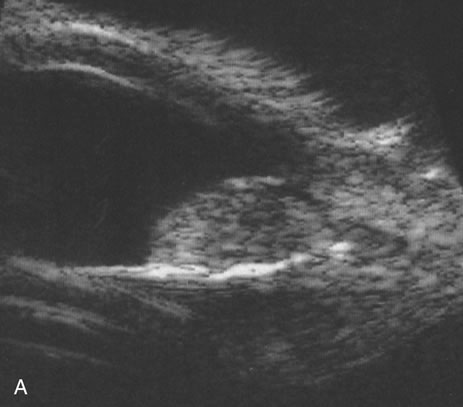

Pseudomelanoma

Melanomas can masquerade as uveitis, and some inflammations or hemorrhagic processes can simulate melanoma. These processes include posterior scleritis, focal choroidal hemorrhage or detachments, and focal scleral thinning. Figures 9 and 10 demonstrate focal scleral thinning in the area of the superior rectus insertion in a patient with rheumatoid scleritis that produced a pseudomelanoma. An apparent elevated pigmented mass was noted on upgaze, but no tumor was observed when the eye was in primary position. Posterior scleritis is often not painful, although some of these patients have deep, piercing pain and increased discomfort during eye movement. Ultrasound usually is diagnostic, demonstrating fluid inside of Tenon's capsule (Fig. 11). A focal hemorrhagic choroidal detachment after cataract surgery can simulate a melanoma. These lesions usually have a bright area of hemorrhage at their base, whereas melanomas typically do not have associated hemorrhage until they break through Bruch's membrane (most commonly, such tumors are more than 5 mm thick). The differential diagnosis of uveal melanoma is discussed elsewhere in these volumes.

Fig. 11. A B-scan showing scleritis adjacent to a proton-irradiated choroidal melanoma.